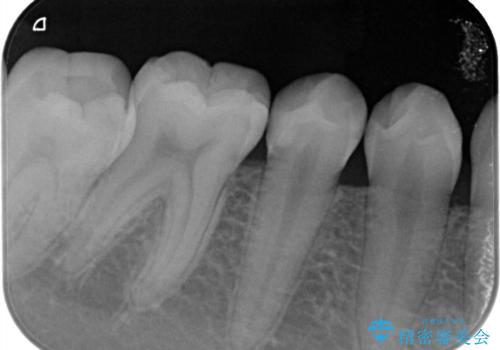

- 定期検診で歯のメンテナンスのため3ヶ月に1回来院されている患者様です。

最近フロスがよく引っかかるとのことでレントゲンを撮ったところ虫歯があり、セラミックインレーにて治療をすることになりました。

虫歯は小さい段階で見つけることが大切です。

早ければ早いほどいいですし、しっかりと型を取って治療することが今後のその歯を再治療しない為のキーになってきます。